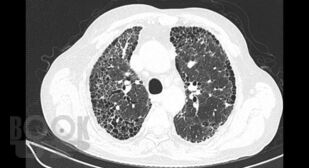

В учебном пособии рассматриваются актуальные и современные вопросы диагностики и лечения интерстициальных заболеваний легких.